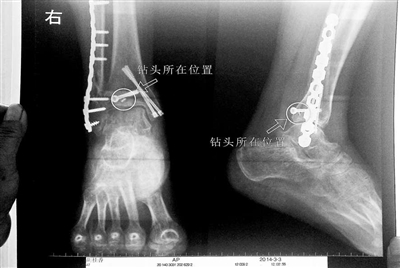

胡女士的腿部X光圖

看著X光片中自己腿內(nèi)的異物,胡女士就感到莫名的擔(dān)憂。胡女士于2013年3月在北京市豐臺(tái)區(qū)右安門醫(yī)院進(jìn)行了一次骨折手術(shù),術(shù)后醫(yī)生才發(fā)現(xiàn)手術(shù)時(shí)用來(lái)打眼用的鉆頭不慎遺留在了胡女士的骨頭中,并且無(wú)法取出。

近日,在豐臺(tái)區(qū)右安門醫(yī)院,北京青年報(bào)記者見到了胡女士,她走起路來(lái)顯得一瘸一拐,腿腳并不利索。在她帶來(lái)的X光片上,可以清晰地看到,有一個(gè)異物存在于腿內(nèi)部。

“我當(dāng)時(shí)就嚇蒙了,怎么會(huì)有一個(gè)鉆頭在骨頭里?”胡女士余悸未消地說(shuō),第二天拍攝的X光片顯示,2厘米左右的鉆頭遺留在她右腳腳踝上部的骨頭內(nèi)。

胡女士說(shuō),當(dāng)時(shí)旁邊的醫(yī)生勸慰自己,稱鉆頭留在腿里并不會(huì)有什么問題。出院后,胡女士每個(gè)月都會(huì)來(lái)醫(yī)院做復(fù)查,拍X光片。她說(shuō),每次都能夠清晰地看見自己骨頭里的那個(gè)明晃晃的“小東西”。

“按照照片里的位置,相對(duì)來(lái)說(shuō)是沒有害的。”豐臺(tái)區(qū)右安門醫(yī)院醫(yī)務(wù)科徐主任告訴胡女士,任何事情都無(wú)法做出絕對(duì)的判斷,但是從目前情況而言,鉆頭對(duì)于腿部沒有更多的危害。她介紹說(shuō),臨床上遇到過很多這種情況,諸如鋼板釘子,有時(shí)候釘子滑扣,無(wú)法取下,也只能存在體內(nèi),但是這些都是個(gè)別情況。

“留在她腿里的鉆頭確實(shí)無(wú)法取出?!毙熘魅谓忉屨f(shuō),按常理說(shuō),鉆頭不應(yīng)該斷在里面,但現(xiàn)在事情確實(shí)發(fā)生了。鉆頭沒有折在關(guān)節(jié),而是在跖骨內(nèi),跖骨主要起支撐作用,不像關(guān)節(jié)那樣起活動(dòng)作用,而且這個(gè)部位比較質(zhì)密,并非像肌肉要經(jīng)?;顒?dòng)受到擠壓。